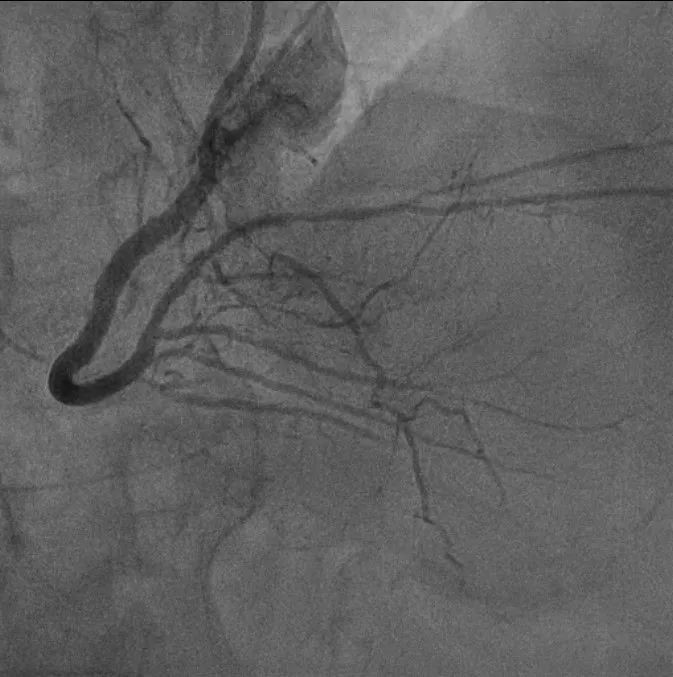

▲右冠状动脉“隧道”成功开通